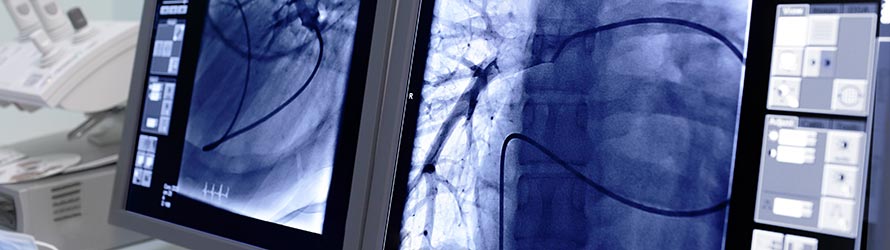

The demands on technological equipment of hospitals and medical offices - especially in radiology - have grown enormously. Radiological images on film are a thing of the past; instead of this method, doctors are making use of systems such as RIS (Radiology Information System) and PACS (Picture Archiving and Communication System). These shortcuts describe the latest developments in the field of paperless and filmless radiology.

Particularly the intelligent interlinking of the latest technology with common standards in the healthcare sector is challenging RIS/PACS systems. These complex structures, operating in the background, have to be easily and rapidly accessible on the user interface. The aim is the optimization of all processes in terms of reducing the workload and saving time, as well for the staff as for the patients.